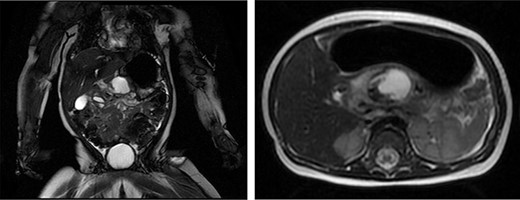

The patient is an 8-month-old otherwise healthy female who presented at 4 months of age with an upper GI bleed. An esophagogastroduodenoscopy revealed a peptic ulcer in D1 with no active bleeding. She was treated with proton pump inhibitors and imaging revealed a mass in the lesser sac with a broad differential including duodenal perforation into the lesser sac possibly from a foreign body, perforation of an upper GI duplication cyst or pancreatitis with pseudocyst formation (Fig. 1). Bloodwork was unremarkable other than elevated lipase at 177 units/L (N < 82 units/L). The presumed diagnosis was a post-pyloric duodenal ulcer and pancreatitis. The infant then re-presented to hospital with new non-bloody emesis and a repeat magnetic resonance imaging (MRI) revealed the same mass in the lesser sac. Further review of the imaging with specialists raised suspicion for a duodenal duplication cyst. The patient then developed signs of cyst infection and a rising WBC count (22.7 × 10^9/L) and was treated with antibiotics. Her vomiting progressed due to GOO secondary to extrinsic compression of the pre-pyloric antrum.